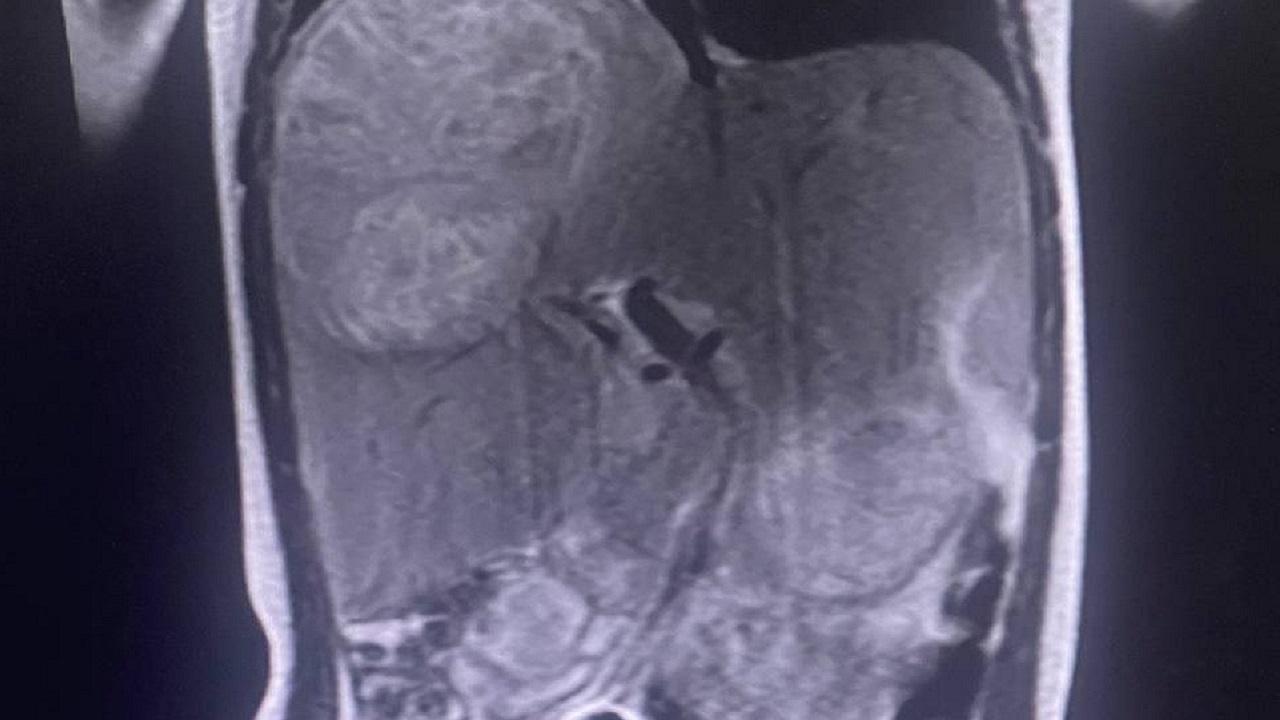

При обследовании был обнаружен многокамерный абсцесс в третьем и четвертом сегментах правой доли печени. Он уже достиг около 10-12 сантиметров (при этом нормальный размер всей печени в этом возрасте составляет 7-8 сантиметров). Предположительно, он возник из-за нагноившейся кисты, в которой были паразиты. При этом увеличенная печень уже начала давить и на другие органы.

"Врачи приняли решение о проведении сложной операции – удалении правой доли печени, не вскрывая абсцесс. Это был единственный способ помочь ребенку, так как абсцесс был многокамерным, и пункция была бы неэффективна. Также удалили и часть диафрагмы, которая из-за воспаления срослась с образованием", – пояснили в пресс-службе ЧОДКБ.